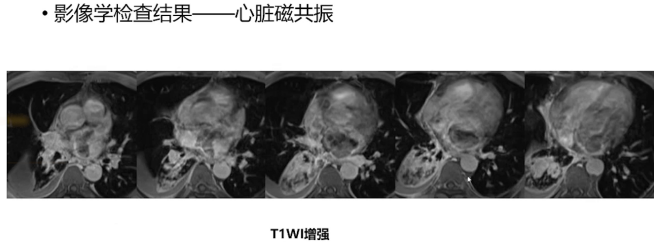

临床经验性治疗肺部感染,期间症状有所好转,胸腔积液逐渐减少,但患者仍感胸闷气短,遂转心内科住院治疗。住院期间胸腔积液量波动且颜色呈洗肉水色改变,肿瘤性病变不能排除,于是进一步完善检查。胸水细菌培养涂片染色等感染相关实验室检查未发现阳性征象。影像学检查方面,胸部CT提示左房内密度不均后,完善超声心动图,发现左房内有中等偏低回声团块影,病变形态不规则,部分位于二尖瓣口但无明显活动性,超声建议进一步行磁共振检查明确左房病变性质。随后患者完善心脏磁共振检查,该检查有多参数,包括常规T2压脂序列、电影序列(通过四腔心、三腔心、两腔心切面显示左房病变),且肿瘤学检查还需常规T1加权增强检查及延迟强化序列。T1加权增强检查发现左房病变有可疑强化,延迟强化序列在十分钟左右可见病变内部散在可疑斑点状强化信号。

2) 鉴别该病变是否为血栓:血栓形成与局部血流动力学异常相关,且存在血栓形成危险因素,误诊血栓为肿瘤会导致不必要治疗,因此需首要排除。磁共振的T1加权延迟强化序列可用于鉴别,血栓信号通常较低,而本病例病变内部有斑点状可疑强化,虽大部分表现为低信号与血栓类似,但内部可强化的实性成分提示并非血栓,因血栓不会强化。

3) 判断肿瘤是否具有特异性特征:若排除血栓,考虑为肿瘤性病变,左房内一些特异性肿瘤在心脏磁共振上信号和毗邻结构有特点。例如,心房囊肿与心房贴近,边界清晰,灌注或强化表现为无灌注或无强化,T2WI信号与液体一致;脂肪瘤有脂肪相关信号,在T1WI、T2WI与脂肪信号一致,脂肪抑制序列信号减低;乳头状弹力纤维瘤附着于瓣膜;黏液瘤是左房常见病变,有蒂状结构,增强后除蒂以外结构基本无血管,整体强化不均匀;黑色素瘤侵袭性高,在T1WI相关序列呈高信号。本病例经鉴别,未发现这些特异性特征。

4) 判断肿瘤的良恶性特征:若肿瘤不具有特异性特征,则需判断其良恶性。良性肿瘤边界清晰,对周围组织结构无侵袭性,有显著均匀强化,T1、T2及灌注特征倾向良性,如横纹肌瘤、血管瘤、副神经节瘤等;恶性肿瘤边界不清,对周围组织结构有侵袭性改变,强化不均匀,T2WI灌注特征更倾向恶性,疾病谱包括血管肉瘤、多形性肉瘤、平滑肌肉瘤、淋巴瘤及转移瘤等。本病例经分析,倾向为恶性病变,其边界不清,几乎充满左房,侵入左房房间隔及右下肺静脉,与周围组织结构分界不清,形态不规则,病变突入肺静脉及二尖瓣口,长轴方向最大截面与后壁关系密切。

对于本病例,综合分析病变与周围组织结构关系后,临床倾向手术处理。手术病理结果为未分化多形性肉瘤,它是第二常见的原发性心脏肿瘤,无性别倾向,多发生于左心房后壁和/或侧壁,大小不等,常较大,偶尔可填充心房腔,可表现为出血性肿块。影像学方面,超声心动图可见广基底肿块伴异质性回声;CT显示左房腔内密度不均匀,表现为大而不规则的腔内低密度肿块,增强检查有相应强化及充盈缺损;磁共振在T1加权像和T2加权像呈等或高信号,但因出血信号特异性不明显,首过灌注和延迟强化可显示不同程度强化,周围可能伴有血栓;PET-CT可用于识别远处转移,因其恶性程度较高可能发生远处转移。